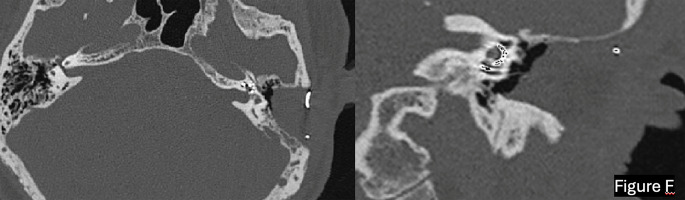

Abstract Image